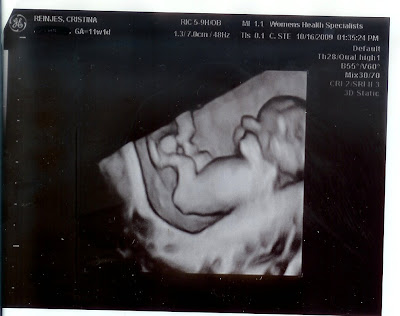

Baby Number 2

Really cool ultrasound last Friday. They did a 3d one, which looks really cool. They say next time we do an ultrasound it will be even cooler.